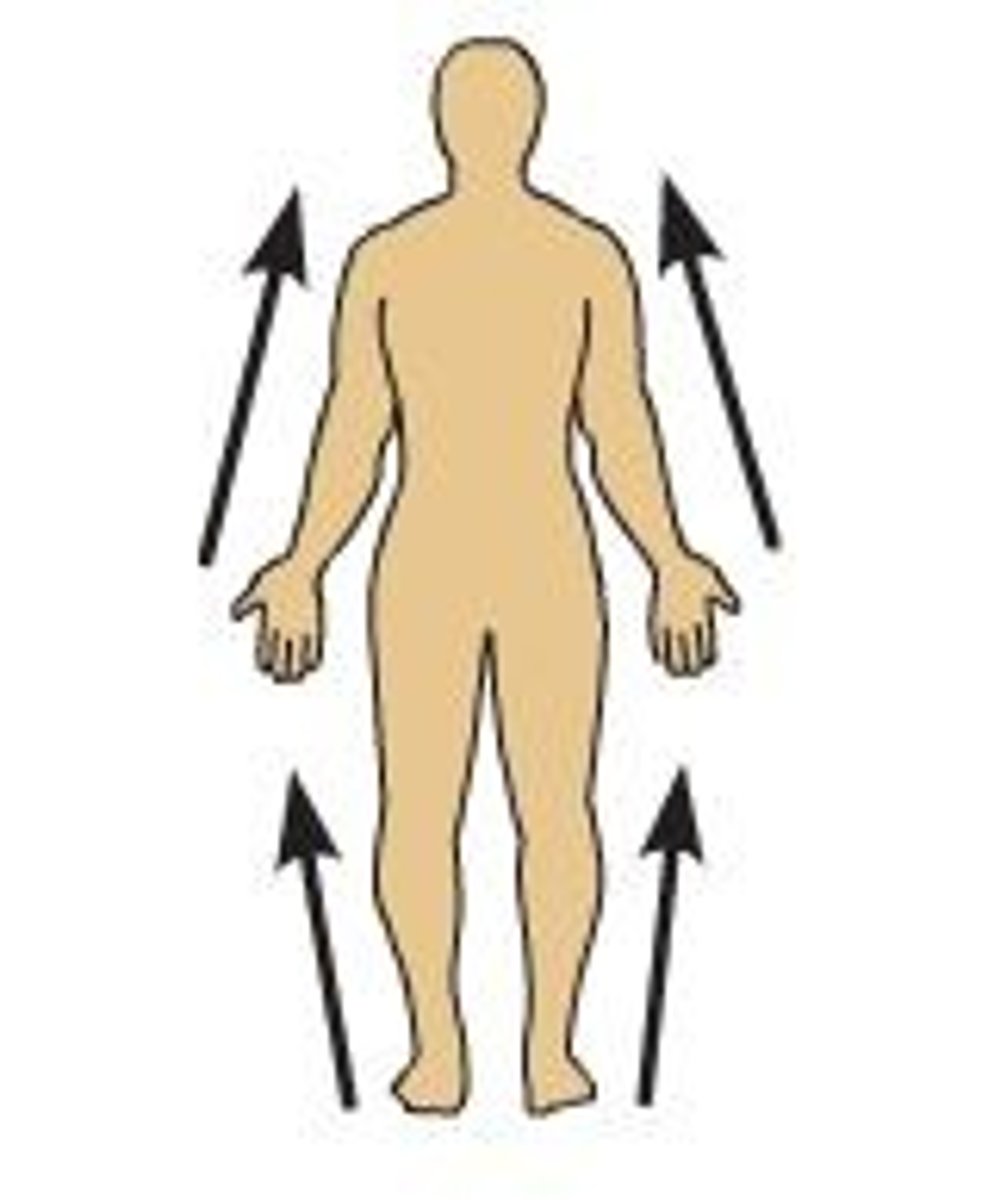

Inferior

Lower on the body, farther from the head

Superior

Higher on the body, nearer to the head

Distal

Farther from the trunk of the body

Proximal

Nearer to the trunk of the body